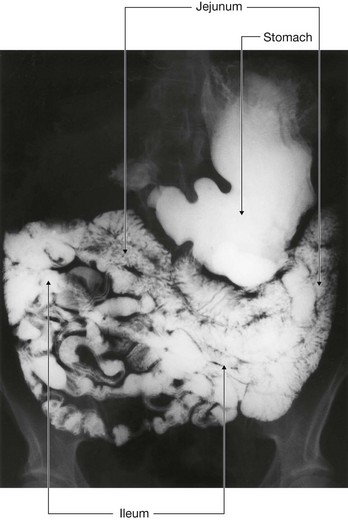

The midgut develops into the distal part of the duodenum, the jejunum, ileum, ascending colon, and proximal two-thirds of the transverse colon. A small yolk sac projects anteriorly from the developing midgut into the umbilicus.

Rapid growth of the gastrointestinal system results in a loop of the midgut herniating out of the abdominal cavity and into the umbilical cord. As the body grows in size and the connection with the yolk sac is lost, the midgut returns to the abdominal cavity. While this process is occurring, the two limbs of the midgut loop rotate counterclockwise around their combined central axis, and the part of the loop that becomes the cecum descends into the inferior right aspect of the cavity. The superior mesenteric artery, which supplies the midgut, is at the center of the axis of rotation.

The cecum remains intraperitoneal, the ascending colon fuses with the body wall becoming secondarily retroperitoneal, and the transverse colon remains suspended by its dorsal mesentery (transverse mesocolon). The greater omentum hangs over the transverse colon and the mesocolon and usually fuses with these structures.